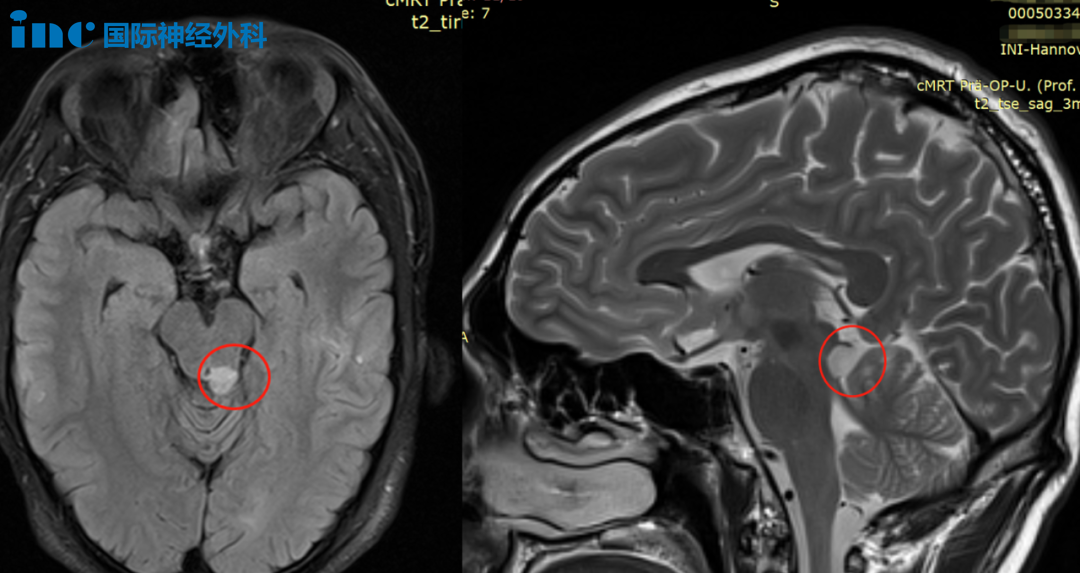

和小永一家不同的是,另一位在胶质瘤病友圈较受关注的周老师治疗更佳积极。四处求医,得到无法手术的回复时,他并没有等。

同样也是脑干胶质瘤,肿瘤不大,但非常棘手。做不好很可能会导致四肢截瘫,甚至不少患者术后躺在ICU里长期昏迷。北上求医,辗转各大医院,依然束手无策。

在得到巴教授可以手术的评估时,他立刻动身,最终安全全切肿瘤,术后第5天顺利出院。如今,总体恢复非常不错,他自豪地说:"我和正常人没什么两样!"